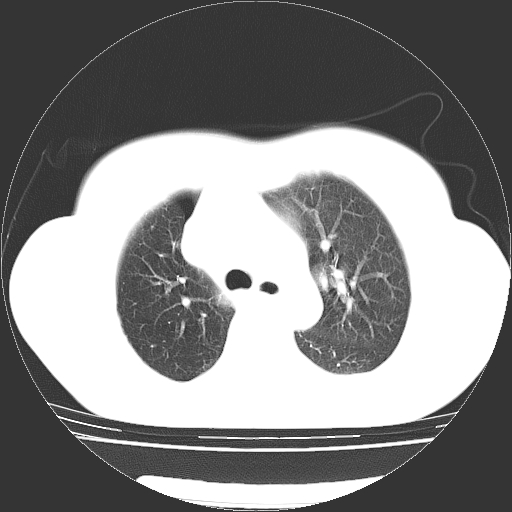

以下是引用zhangzhongshou在2008-3-22 12:52:00的发言:[br]1、右侧液气胸。[br]2、腹水。建议进一步检查。

以下是引用鲁巨ct在2008-3-22 14:10:00的发言:[br]1、右侧液气胸,右中下叶节段性不张。[br]2、腹水,建议上腹部ct检查

以下是引用zjzjr在2008-3-22 17:19:00的发言:[br]1、右侧液气胸,右下叶节段性不张。[br]2、腹水,建议上腹部ct检查